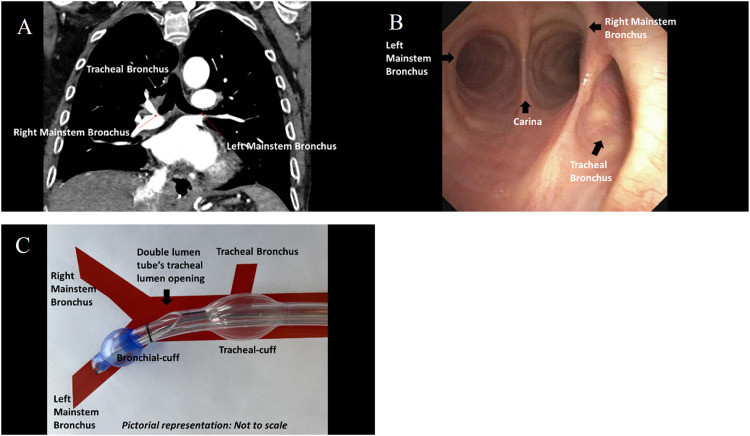

A tracheal bronchus is an anomalous or accessory bronchus that arises directly from the supracarinal tracheal wall. When the tracheal bronchus supplies the entire right-upper-lobe, it is referred to as bronchus-suis (pig-bronchus). This tracheobronchial arrangement, commonly found in pigs, is rare in humans with a reported incidence of 0.2%.1 The accompanying images demonstrate this anatomical variation of the tracheobronchial tree (Fig. 1: Panel A and B) and are from a patient who needed right lung isolation during an esophagectomy.

Radiographic imaging (Panel A) and bronchoscopy (Panel B) demonstrate carinal bifurcation into left mainstem bronchus and right mainstem bronchus and presence of a supracarinal tracheal bronchus originating from the right tracheal wall. When establishing right lung isolation with a left-sided double-lumen-tube, the aberrant tracheal bronchus is at risk of being obstructed by the left-double-lumen-tube's tracheal cuff, especially if its opening lies proximal to or at the level of the tube's tracheal lumen opening, as seen in the pictorial representation (Panel C).

Achieving satisfactory right lung isolation in patients with bronchus-suis morphology may be challenging. As the right-upper-lobe does not arise from the right-mainstem-bronchus, a right-sided double-lumen-tube would only facilitate isolation of the right-middle and lower-lobes. Consequently, bronchoscopy guided placement of left-sided double-lumen-tube is preferred. With the bronchial-cuff positioned just below the carina, right lung isolation is achievable when the tracheal-bronchus's opening remains distal to the tube's tracheal-cuff. If the tracheal-bronchus is situated proximal to or at the level of the tube's tracheal-cuff, obstruction of it's opening by the inflated tracheal-cuff, may hinder right-upper-lobe collapse (Fig. 1: Panel C). In such circumstances, it may be necessary to place a single-lumen-tube and guide individual bronchial blockers into the right-mainstem-bronchus and tracheal-bronchus to achieve right lung isolation.2,3